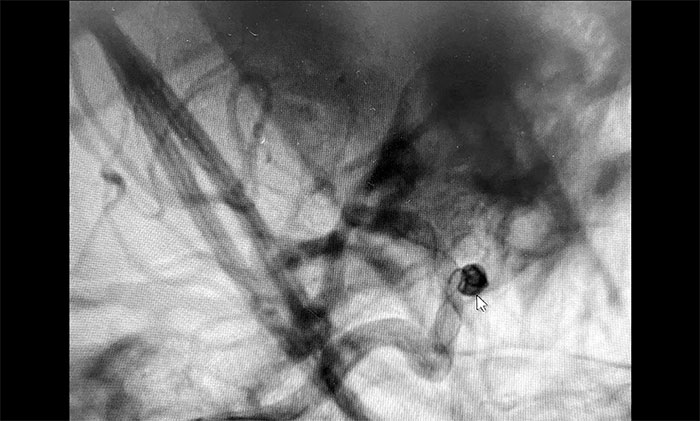

▲动脉瘤栓塞

术中,在微导丝的引导下将微导管头端小心送入动脉瘤腔内,之后顺着这个通路往动脉瘤内填塞弹簧圈,造影显示动脉瘤瘤内造影剂明显滞留,眼动脉(载瘤动脉)血流通畅。遂解脱弹簧圈并释放支架,再次造影,支架覆盖动脉瘤,贴壁良好。整台手术历时90分钟顺利完成,患者术后恢复情况良好。